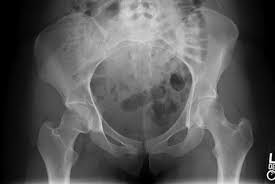

Cancer can also cause the following symptoms: Symptoms of ovarian cancer usually develop for a long time in the body without manifestations. Cancer in the back, pelvis, and lower extremities can spread to the inguinal lymph nodes. The groins are also on either side, around the crease where the leg joins the rest of the body. Many lymph nodes are located in the head and neck area.

A dull ache in the abdomen or groin. If you are a woman who is experiencing pain in your groin, a wide variety of conditions may be to blame. A normal lump that is due to injury or even a body growth shrinks or goes away in very few days. Cancer can also cause the following symptoms: In fact, many of the symptoms of colorectal cancer can also be caused by other problems, such as infection, hemorrhoids, irritable bowel syndrome, or inflammatory bowel disease. However, other health conditions can also cause the same symptoms 2. Symptoms of bladder cancer in women. Symptoms in this part of the body can be for many different cancers. Ask for a transvaginal ultrasound if you suspect something more than routine heavy periods. Since christmas that the lump in my groin was a cyst then a hernia then a femeral hernia then lymphoma and then after a week. If groin lumps result from abscesses or serious infections, these can lead to widespread infection throughout your body if left untreated. Groin pain can be a symptom of advanced cervical cancer, which potentially signals metastasis. Also there is a group of glands in the groin area, which normally cannot be felt.

The abdomen may feel very full or heavy, and the person may also have lower back pain. Swollen lymph nodes in groin female. A more common cause is rupture of the fallopian tube in case of ectopic pregnancy, which usually causes severe pain and bleeding. Certain types of cancer—testicular cancer, melanoma (skin cancer), or lymphoma—can also cause lumps in the groin. 12 dec 2016 19:54 in response to edith1. A feeling of heaviness in the scrotum. Cancer can also cause the following symptoms: This is known as radiating or referred pain. Spinal cord tumors are most commonly found in the thoracic region of. Groin pain can occur when the cancer spreads into the bones or other areas of the groin, triggering frequent pain that ranges. Unfortunately, many women also said their doctors weren't responsive, overlooking or misdiagnosing their complaints as normal perimenopause. Also there is a group of glands in the groin area, which normally cannot be felt. However, other health conditions can also cause the same symptoms 2.